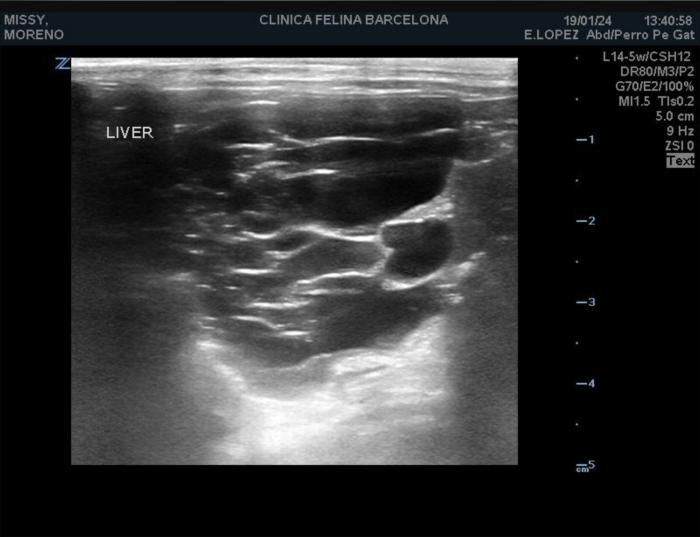

Ecográficamente, los quistes se visualizan como estructuras redondas u ovaladas, de tamaño variable (desde menos de 1 mm hasta más de 1 cm), con la pared fina y contenido anecoico con fuerte refuerzo acústico posterior. La mayoría se localizan en la corteza y en la unión corticomedular de uno o ambos riñones. Con el paso del tiempo, los quistes aumentan en número y volumen, sustituyendo el parénquima normal e incluso llegando a deformar el contorno renal. En algunos casos se pueden desarrollar quistes en el hígado y/o páncreas (4)(6)(8) (Figura 4). En nuestro paciente, ecográficamente se observaron ambos riñones irregulares y con quistes, sin lesiones en hígado ni tampoco en páncreas.

Los hallazgos laboratoriales en individuos con ERP son compatibles con una enfermedad renal crónica (ERC). El análisis de sangre suele revelar anemia, azotemia e incremento de la concentración sérica de fósforo. La densidad urinaria tiende a ser baja y puede aparecer proteinuria. La radiografía permite confirmar la presencia de cambios en el tamaño de los riñones. La aparición de signos clínicos asociados con insuficiencia hepática, debido a la presencia de quistes en esta localización, no es habitual(3). En nuestro caso, la palpación renal era anormal y analíticamente destacaba una anemia leve no regenerativa, azotemia y densidad urinaria baja.